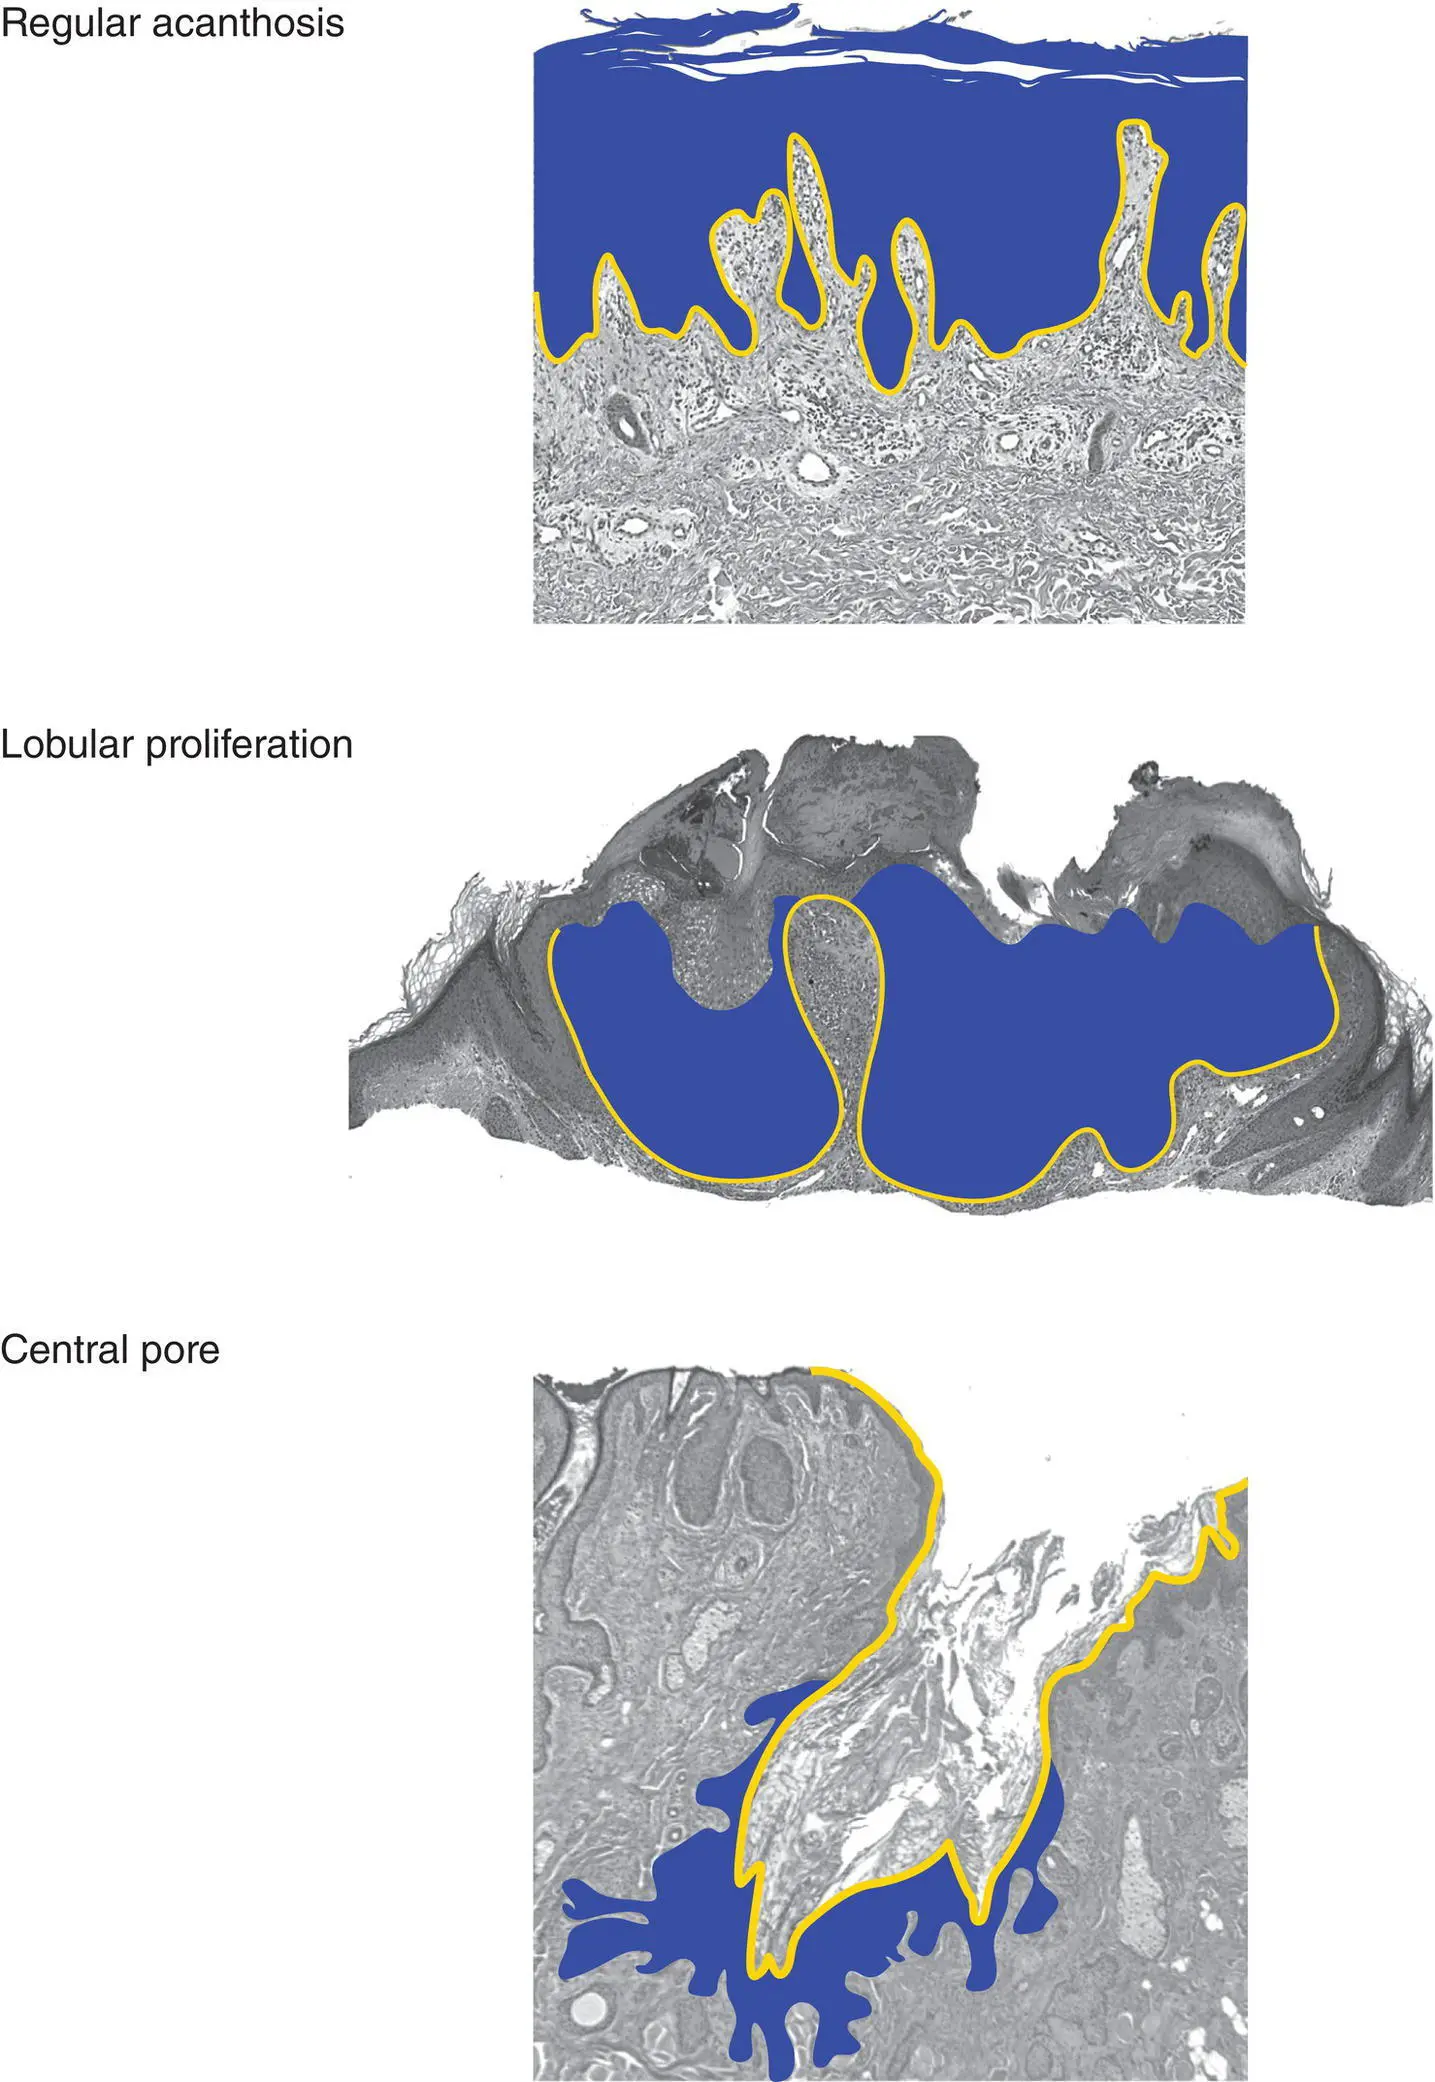

Figure 2(B)Architecture of an epidermal tumor/process

Dermal tumors can have various architectural patterns

NoteBenign tumors are often symmetric with a pushing border, and malignant tumors may be asymmetric and infiltrative.

Figure 3(A) Key epidermal changes

Parakeratosis: retained nuclei in the stratum corneum

Spongiosis: increased intercellular spaces and sometimes vesicles

Papulosquamous: thickened epidermis with parakeratosis

Interface (vacuolar): spaces in basal cells, which may be polygonal (squamatized), lymphocytes at junction

Interface (lichenoid): dense band of lymphocytes between epidermis and dermis with necrotic keratinocytes